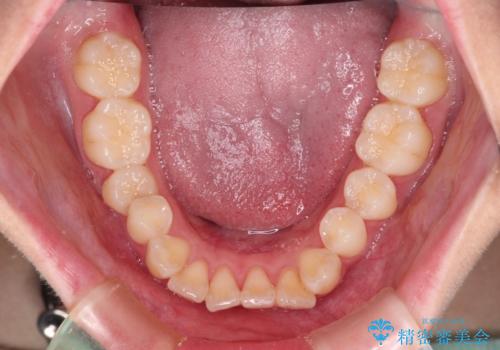

- 前歯がくちばしのように飛び出していることを気にして来院された患者様です。

唇が前方に突出している横顔が気になっているため、上下左右の第一小臼歯4本を抜歯し、ワイヤー装置にて矯正治療を行うこととしました。